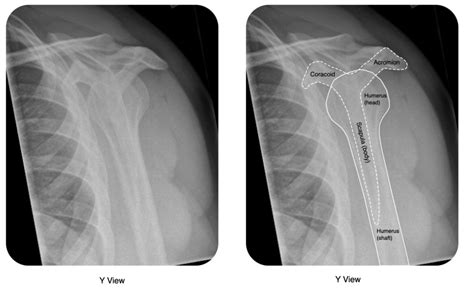

What the X-Ray Shows

When the X-ray image is developed, the doctor will be looking for several key things. First and foremost, they want to see if the head of the humerus is indeed out of its socket. A normal shoulder X-ray will show the head of the humerus sitting snugly within the glenoid fossa. If it’s dislocated, the humerus will be displaced, often sitting in front of or below the socket. Secondly, they’ll be on the lookout for fractures. Fractures can occur in the humerus itself, the glenoid, or even the clavicle (collarbone), which is closely connected to the shoulder joint. The X-ray can reveal the type and severity of these fractures, which is vital information for planning treatment. Lastly, the X-ray can sometimes show other issues, such as pre-existing conditions like arthritis or bone spurs, which might influence the management of the dislocation. So, it’s a really comprehensive look inside your shoulder!

The primary goal of an X-ray in this scenario is to confirm whether a dislocation has occurred. A normal shoulder joint will show the head of the humerus (the ball) sitting neatly within the glenoid fossa (the socket). When a dislocation is present, the head of the humerus will be displaced, meaning it has popped out of the socket. The X-ray will clearly show this displacement. There are different types of shoulder dislocations, most commonly anterior (where the humerus moves forward) and posterior (where the humerus moves backward). The X-ray will help identify the direction of the dislocation, which is important for guiding treatment. It’s like having a map that shows exactly where the ball has rolled off the track. This visual confirmation is crucial for accurate diagnosis and planning the reduction (putting the shoulder back in place).